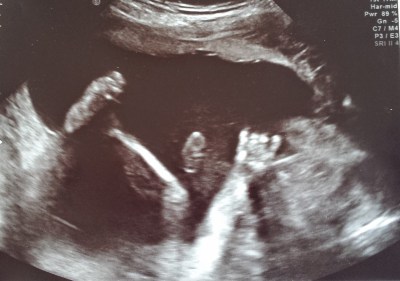

Our ultrasound tech told us that she wasn’t able to get a good shot with the 3D camera, but she was able to tell, with “93% accuracy, ha-ha,” what sex our baby was. She printed off a picture with this crucial information and put it into an envelope. We left, giddy and giggling.

![]() |

| IT’S A BOY!!!!!!!!!!! |